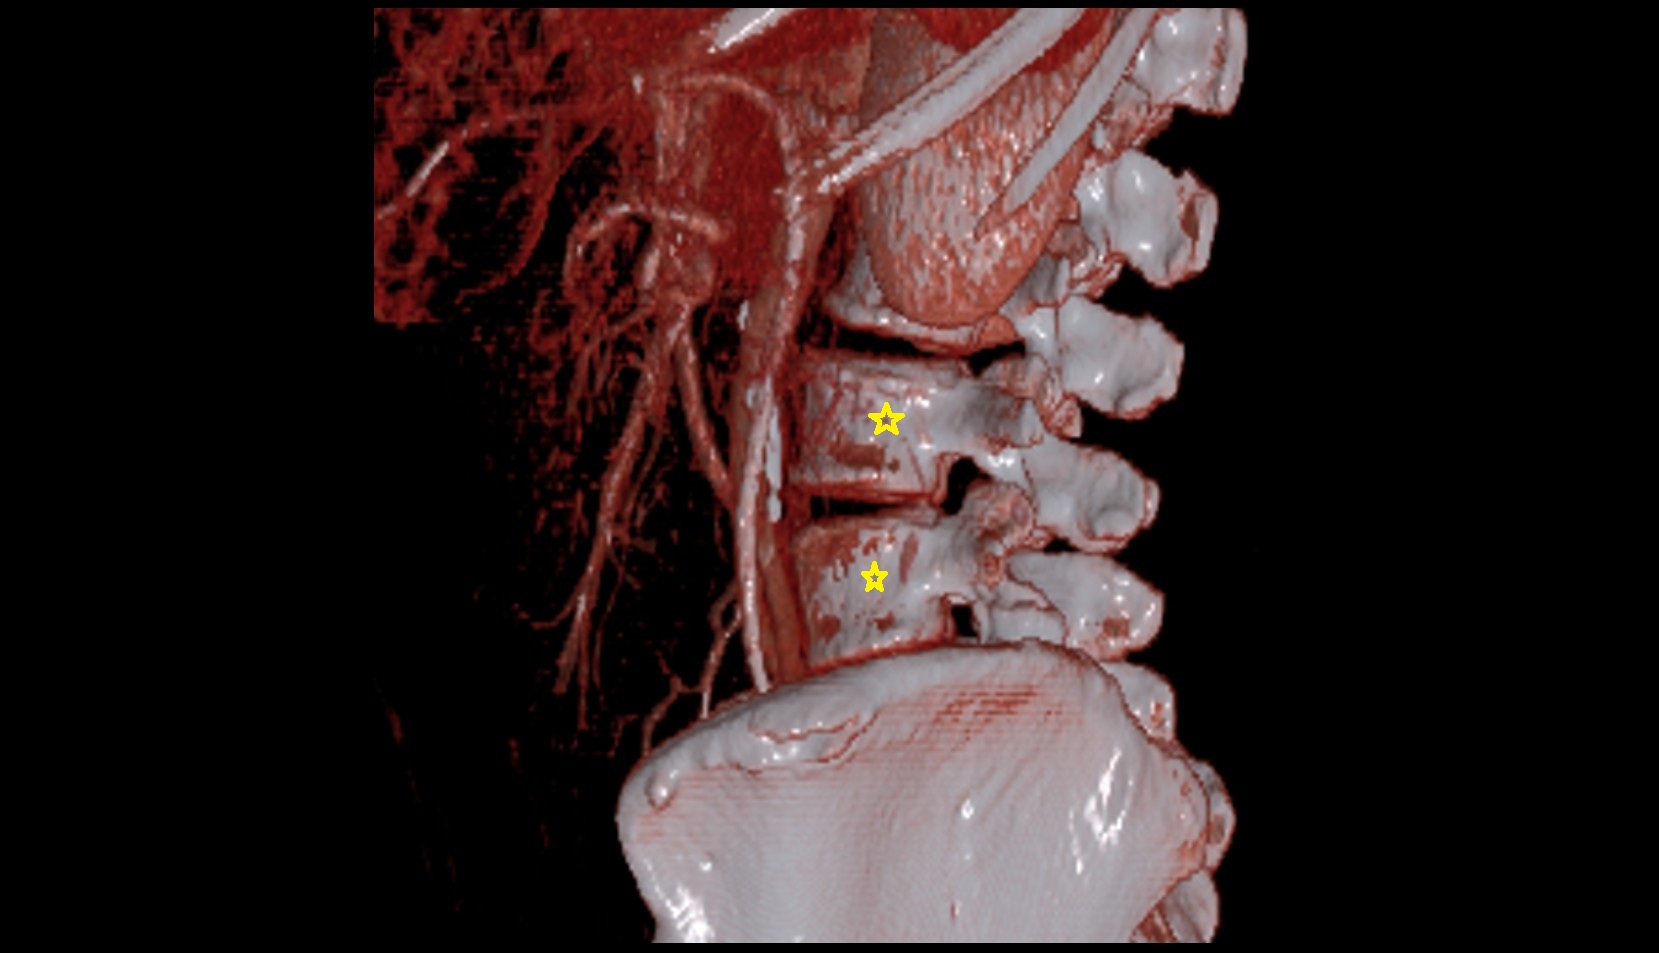

- Right vertebral artery

- Left vertebral artery

- Right vertebral artery (cervical part)

- Right vertebral artery (atlantic part)

- Left vertebral artery (atlantic part)

- Left vertebral artery (cervical part)